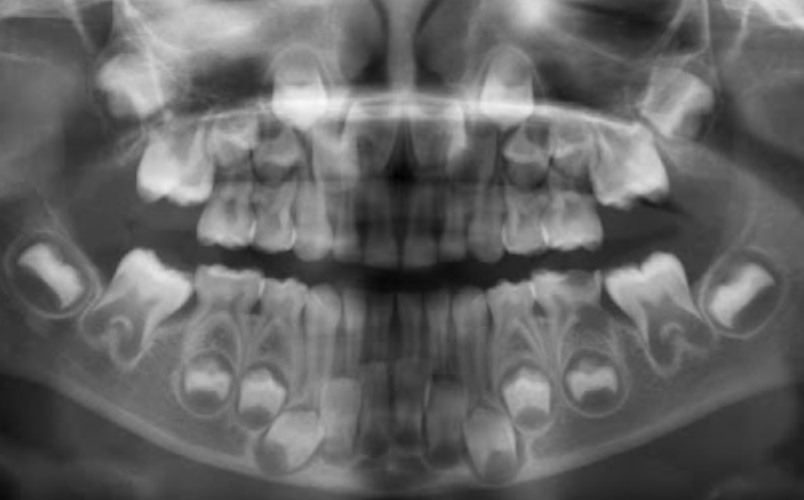

1.Lower adult CI there? YES. so def 6-7

1. Upper adult CI there (they normally erupt 7-8)? NO, baby ones should shed at 6-7.

Conc: pt. Is 6 y.o